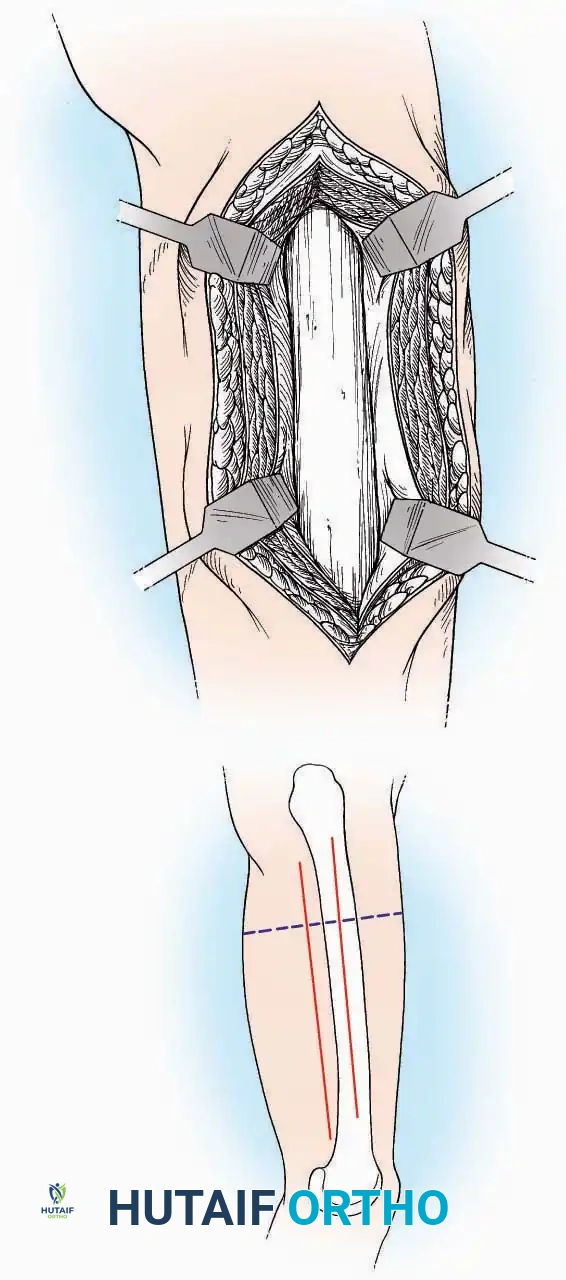

Anterior Approach

Indications: Total ankle arthroplasty (TAA), anterior ankle arthrodesis, and excision of anterior tibial/talar osteophytes (anterior impingement).

Surgical Technique:

* Incision: Make a 10 to 15 cm longitudinal incision over the anterior aspect of the ankle, centered exactly midway between the medial and lateral malleoli.

* Superficial Dissection: Incise the superficial fascia. Identify and protect the superficial peroneal nerve branches laterally and the saphenous nerve medially.

* Internervous Plane: The deep dissection exploits the plane between the Extensor Hallucis Longus (EHL) tendon (innervated by the deep peroneal nerve) and the Extensor Digitorum Longus (EDL) tendons (also innervated by the deep peroneal nerve).

* Neurovascular Bundle: Incise the extensor retinaculum. Carefully identify the anterior tibial artery and the deep peroneal nerve, which typically lie between the EHL and EDL, or directly deep to the EHL. Retract the neurovascular bundle laterally with the EDL, or medially with the EHL, depending on the specific anatomical variant encountered (lateral retraction is most common).

* Capsulotomy: Incise the anterior joint capsule longitudinally. Elevate the capsule subperiosteally from the anterior tibia and the talar neck to expose the entire tibiotalar articulation.